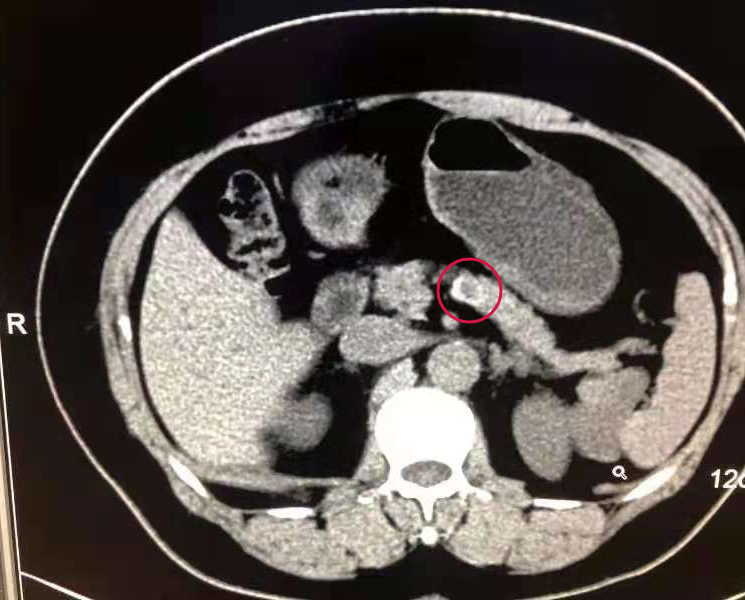

腹部CT平扫+三维重建:胰腺体部低密度影伴边缘钙化,胰尾后方低密度影?建议进一步增强CT;

增强CT,检查结果为胰腺体部及尾部异常密度影,考虑占位,胰岛细胞瘤?如下图:

临床分析:患者检测血糖低至2.8mmol/L,胰岛素基础水平增高,胰岛素释放指数大于0.3,住院期间在给予葡萄糖液补充的同时,血糖也仅为5mmol/L左右,补充的葡萄糖去向何处?经患者的临床表现及相关辅助检查,同时结合影像学结果,患者诊断为胰岛素瘤,转入普外科手术治疗。

| 这是个很典型的胰岛素瘤的案例,是血糖和胰岛素之间的关系。临床上血糖降到2.8mmol/L时,就不应该有胰岛素的分泌,这个时候分泌的为胰高糖素,血尿儿茶酚胺,如果血糖继续下降还有糖皮质激素和生长激素分泌增多。临床上根据实验室检查结果和临床表现给患者的诊断提供了方向,同时结合影像学确诊。检验人员在平时工作中面对一些异常报告单时,如果通过检验和临床结合,就能发现不同领域的知识点,从而更好地辅助于临床。 |